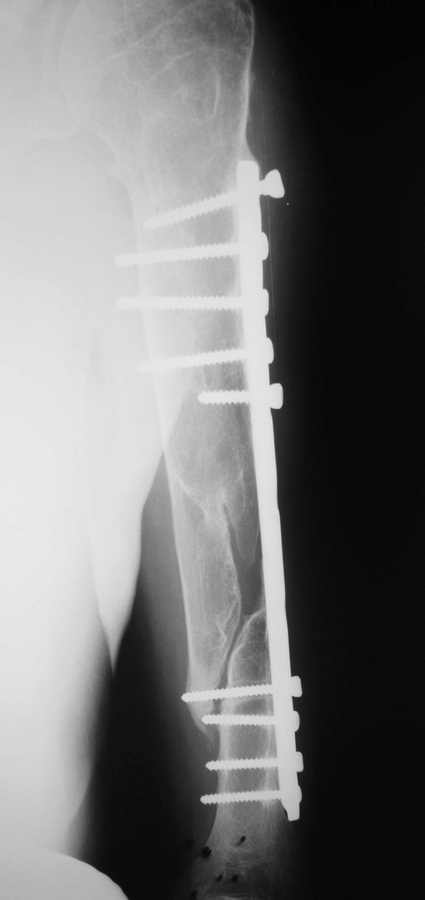

ложный сустав плеча.

Травма и операция два года назад.

Показан реостеосинтез. Выбор фиксатора?

Жалко, что дистальный конец плечевой кости в снимок не вошел. И нет данных о больном. А вообще было бы интересно передвинуть пластину дистальнее на 2-3 отверстия и поставить новые винты подальше от ложного сустава. Бюджетный и малотравматичный вариант. И костная пластика, естественно.

вот и у меня сомнения - а ложный ли сустав? Можно посмотреть вторую проекцию?

Все , конечно, в жизни бывает, но пока что все ложные суставы плеча, виденные мной, имели либо поломанную пластину( редко), либо ( часто) - пластина вырвана из кости

100 % апластический ложный сустав, перелом пластины дело времени и усталости металла. Реосинтез здесь очень серьезное мероприятие, недавно на сайте уже обсуждали подобную ситуацию со всеми вытекающими осложнениями.

Проблема здесь в питании зоны перелома, нет контакта отломков, нет микроподвижности для стимуляции мозоли, сосуды ободраны вместе с надкостницей во время операции. Повторно "перекручивать" пластину это все равно, что прыгнуть в пустой бассейн с 3х метровой вышки, полежать(2 года:) подумать и прыгнуть еще раз , но уже с 5 метровой вышки, так уж наверняка.

Оптимально: убрать пластину, "расшуровать" зону перелома, БИОС с укорочением, до хорошего контакта отломков с такой образной компрессией, если молодой можно остановиться, дать раннюю нагрузку, ЛФК, кальцием покормить + сосудистые препараты. В идеале (как в Питере делают) на сосудистой ножке вшить трансплантат из малоберцовки, но это хирургия высокого полета, не для каждого аэродрома ( больницы :).

На недавней конференции в Киеве прозвучала лекция, в которой в том числе рассматривались вопросы несращения, ложных суставов и костной пластики. Рекомендации таковы: при апластическом ложном суставе резекция концов фрагментов, БИОС с рассверливанием, костная пластика в таких условиях эффективна только на сосудистой ножке, свободная КП не эффективна.